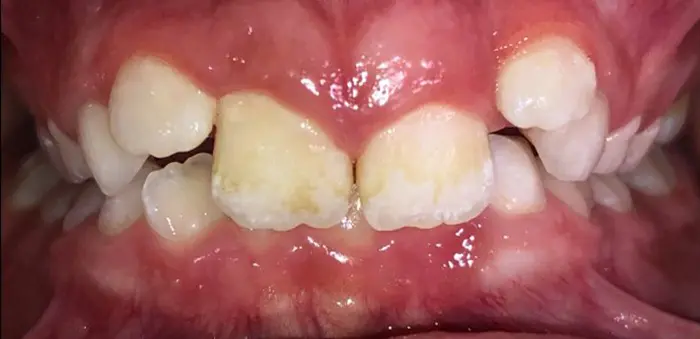

Actual Patient: Alexander

Alexander Before 4 Alexander After 4

Severe “Underbite”, Narrow Jaws, Adult Teeth Not Growing In

Alexander Before 1 Alexander After 1

Front View

Top View

Right & Left Sides